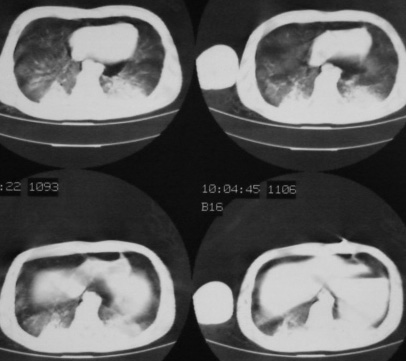

男,18岁,车祸20小时后胸ct.血氧饱和度80,呼吸45次/分.

1:双肺挫裂伤,以双下肺明显。

2:纵隔气肿。

1:两侧创伤性湿肺。

1.双肺挫伤,2.纵隔积气。注意右侧主支气管是否有断裂?